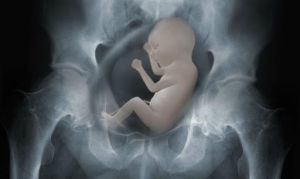

| 極軟X射線 | 5~20 | 0.25~0.062 | 軟組織攝影、表皮治療 |